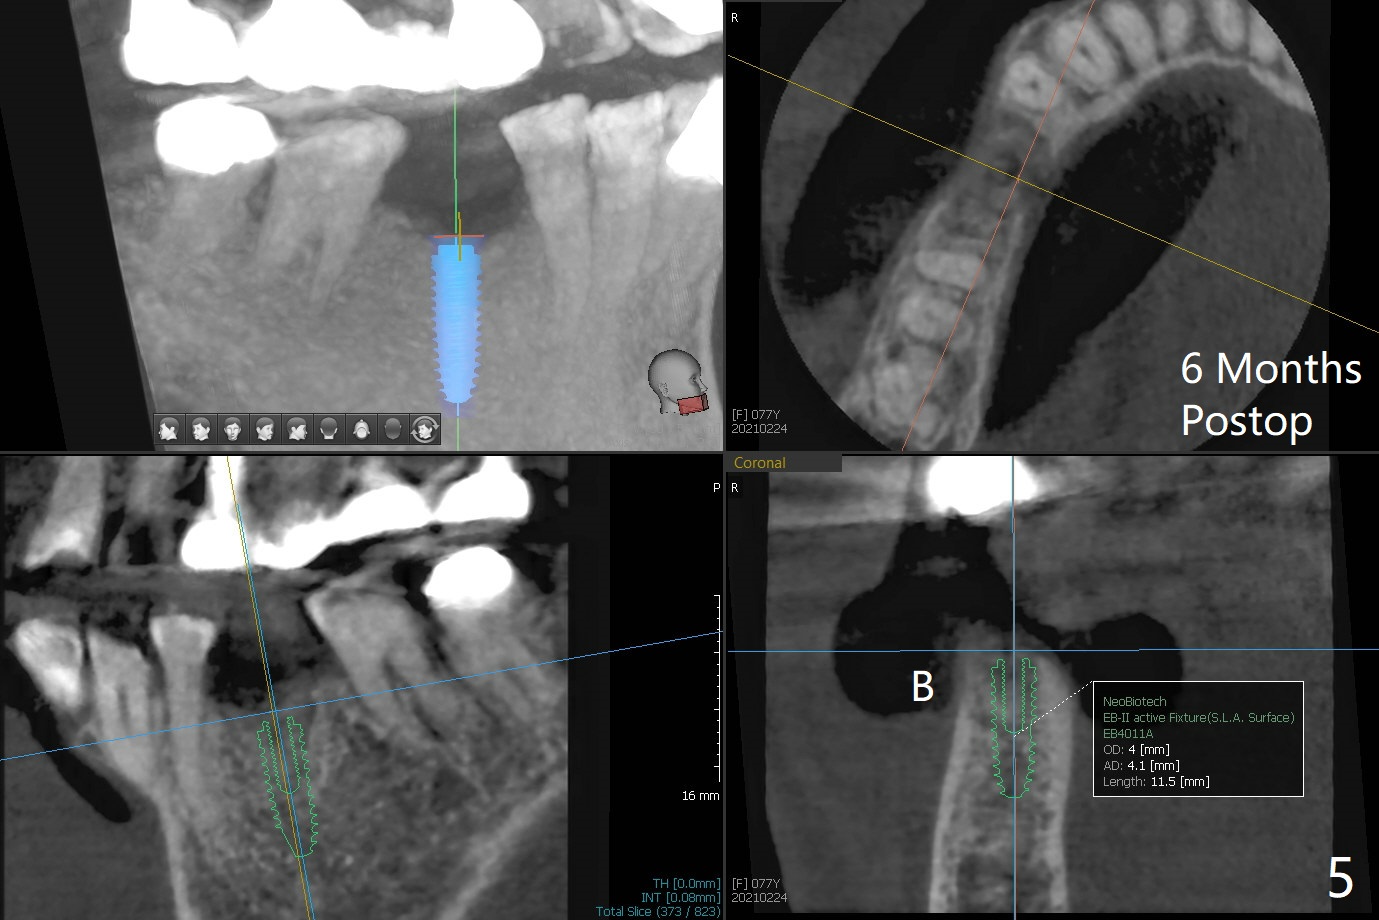

A 77-year-old woman agrees to have the lower right 2nd premolar extracted after lengthy delay (Fig.1,2 buccolingual plate present, but low) and grafted (Fig.3 *).  Cortical graft is heavily packed, covered by a small piece of 6-month membrane and sutured with 4-0 Chromic gut suture.  The socket is closed 7 days postop (Fig.4).   The buccal plate seems to have been reformed 6 months postop (Fig.5,7, as compared to Fig.6 (pre-fracture)).  Return to No Deviation Surgery  Xin Wei, DDS, PhD, MS 1st edition 08/19/2020, last revision 05/12/2021